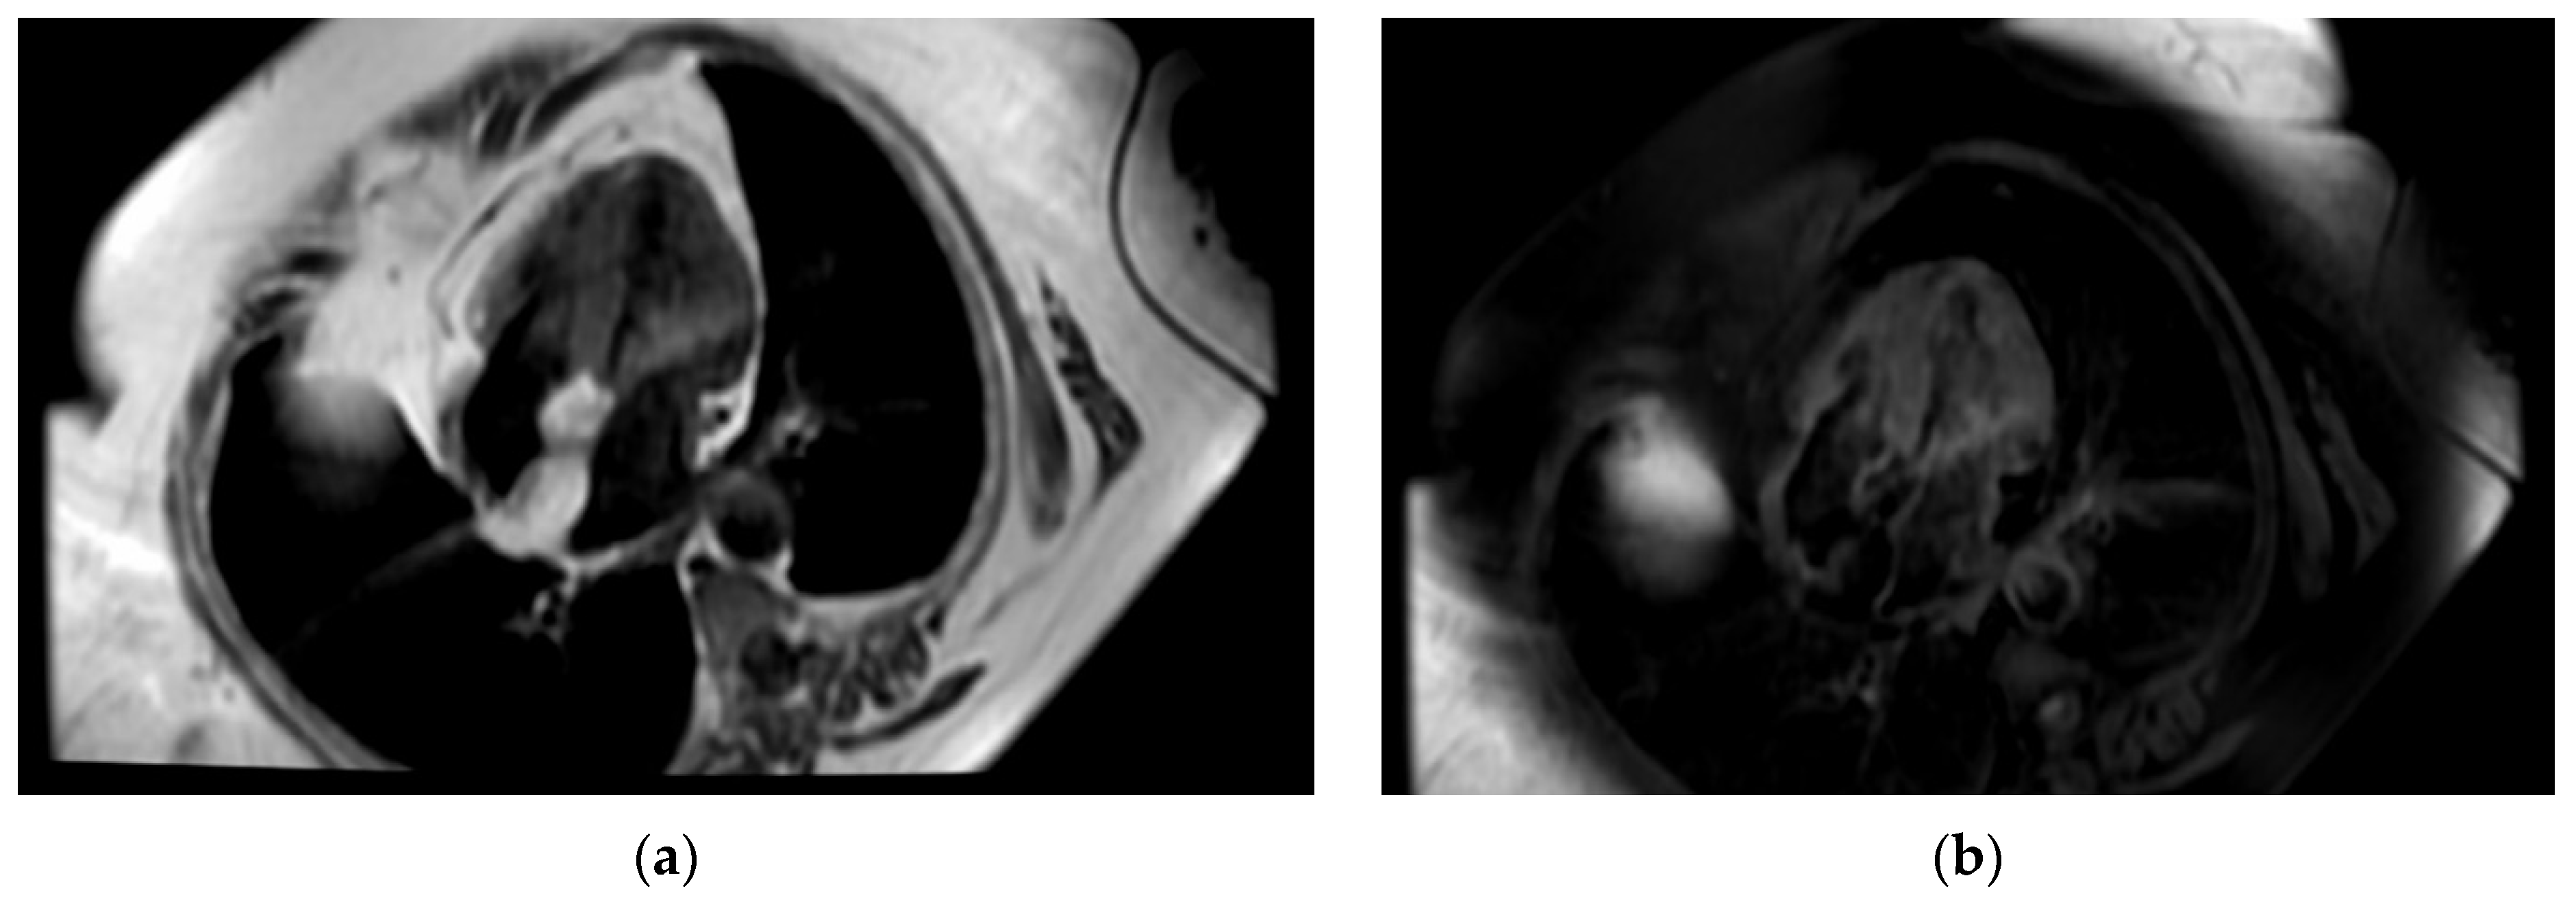

Even though the diagnosis was suspected, a cardiac magnetic resonance was performed in order to be accurate, given the implications a wrong diagnosis might have had. The “hourglass” aspect of the IAS with significant hypertrophy was confirmed in the cine-balanced steady-state-free precession (bSSFP) sequences. There was no contrast up-take at this level, suggesting a lack of vascularization, and the structure showed a high signal in T1 and a low/isointense signal in T2 with a very similar aspect to the very well-represented pericardial and mediastinal fat (Figure 4, Figure 5 and Figure 6). The diagnosis of lipomatous hypertrophy of the interatrial septum was established.

Figure 4.

Cardiac MRI. (a) Four-chamber-view, steady-state-free precession image revealing interatrial septal hypertrophy—25 mm with “chemical shift”; (b) perfusion image—no caption of contrast at first-pass contrast.

Figure 5.

Cardiac MRI. (a) Double-inversion-recovery T1 sequence (4 chambers) revealing a hyperintense interatrial septum suggestive of fat; (b) double-inversion T1 sequence with fat suppression revealing a hypointense interatrial septum.

Figure 6.

Cardiac MRI. (a) Triple-inversion-recovery T2 sequence of isointense interatrial septum; (b) late gadolinium enhancement (LGE)—enhancement in interatrial septum.